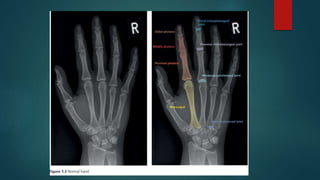

Skeletal X ray anatomy ,colour description, Imaging anatomy of musculoskeletal X rays, Diagnosis imaging anatomay, Radiology